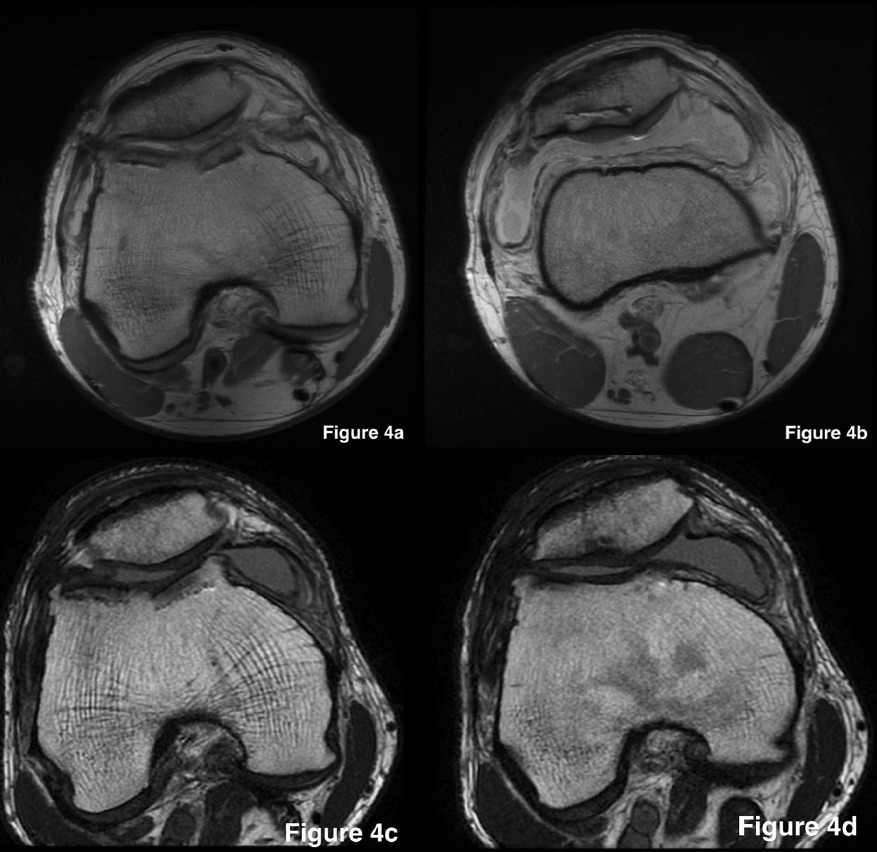

We routinely obtain a magnetic resonance imaging (MRI) assessment at 6 months to assess graft morphology. Osseous integration is not expected to be complete at this time.83 However, at 6 months, the allograft should show an intact articular cartilage surface, progressive bony incorporation with evidence of cross trabeculae, and no joint effusion (Figure 10). These objective measures, along with good movement, sufficient quadriceps control, and minimal (<20%) side-to-side strength differences, form our basis for permitting athletes to start high-impact activities such as running and other sport-specific tasks. Progression should be in a planned and organized manner, so the athlete has specific stages to progress through with the goal of returning to the field of play. Activities should start with planned non-reactive drills (cone drills, set passing drills) and progress to unplanned reactive drills. While extra precautions should be taken for contact sports during this phase, play on the field may be initiated with non-contact scrimmage, progressing to contact scrimmage, and lastly, controlled live play. When these steps are completed and proper loading and confidence is seen in the athlete, along with no signs of deleterious effects on the knee joint, the athlete can progress to full game play.

_on_postoperative_day_one_after_oca_of_the_(a)_troc.png)